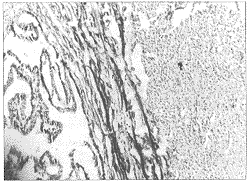

输卵管平滑肌瘤1例

输卵管肿瘤是少见的妇科肿瘤 ......